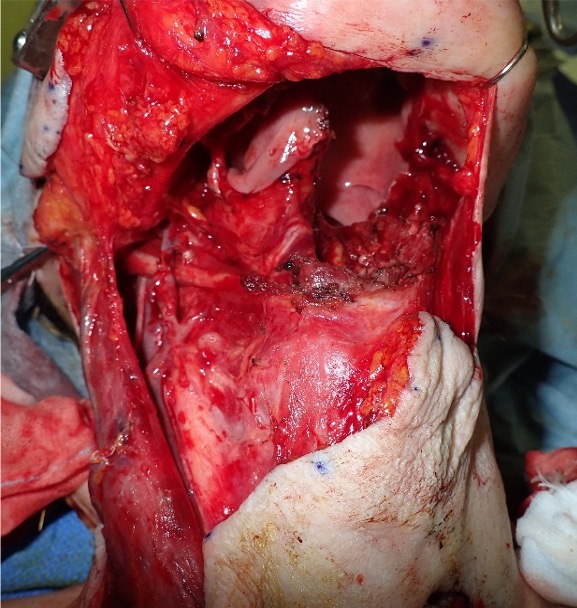

The patient underwent otolaryngological surgery for subtotal removal of the left side of the tongue and right cervical dissection (Figure 1). Due to her history of multiple cervical surgeries, advanced age, and susceptibility to infection, she had a high risk of necrosis with damage and adhesion in the recipient vessel after surgery. The authors judged that free tissue transfer would not be suitable; accordingly, the PMMC flap was chosen.

The lateral thoracic artery was identified by the descending lateral border of the pectoralis major. The lateral thoracic artery was cut at the branch of the subclavian artery and was preserved in the flap (Figure 2B). An intravenous injection of 2 mL ICG (2.5 mg/mL; Diagnogreen; Daiichi-Sankyo Pharmaceutical) was administered to the patient. Three minutes later, a staining defect was observed on the caudal side of the flap, and a supercharged PMMC flap was used (Figure 2C). The flap was moved into the oral cavity, and the lateral thoracic artery was anastomosed with the superior thyroid artery under microscopic visualization (Figure 3).